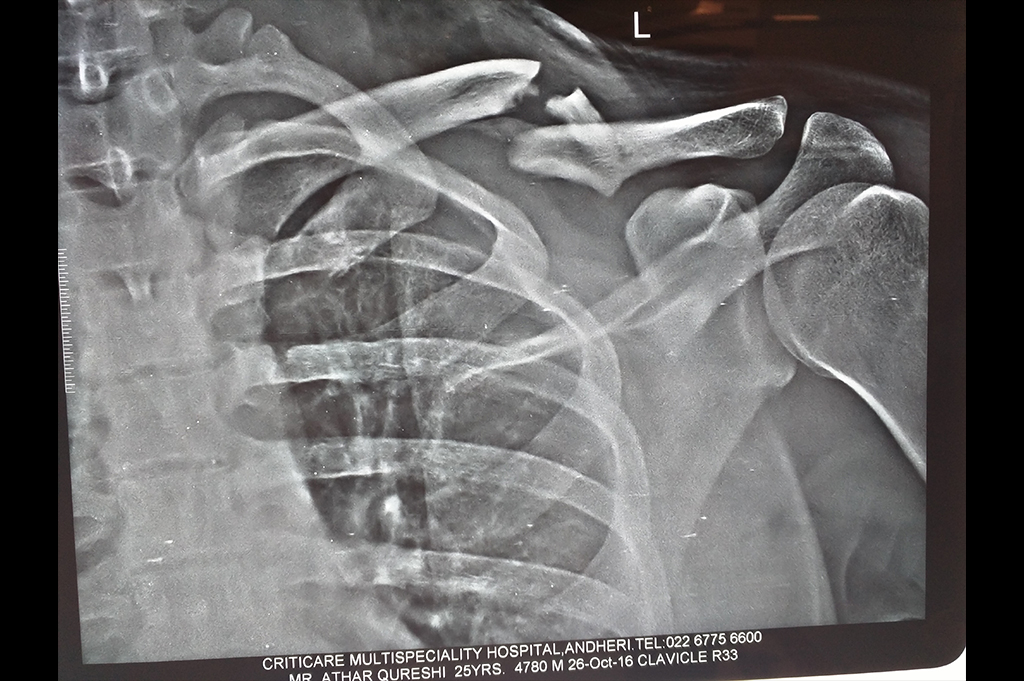

Clavicle